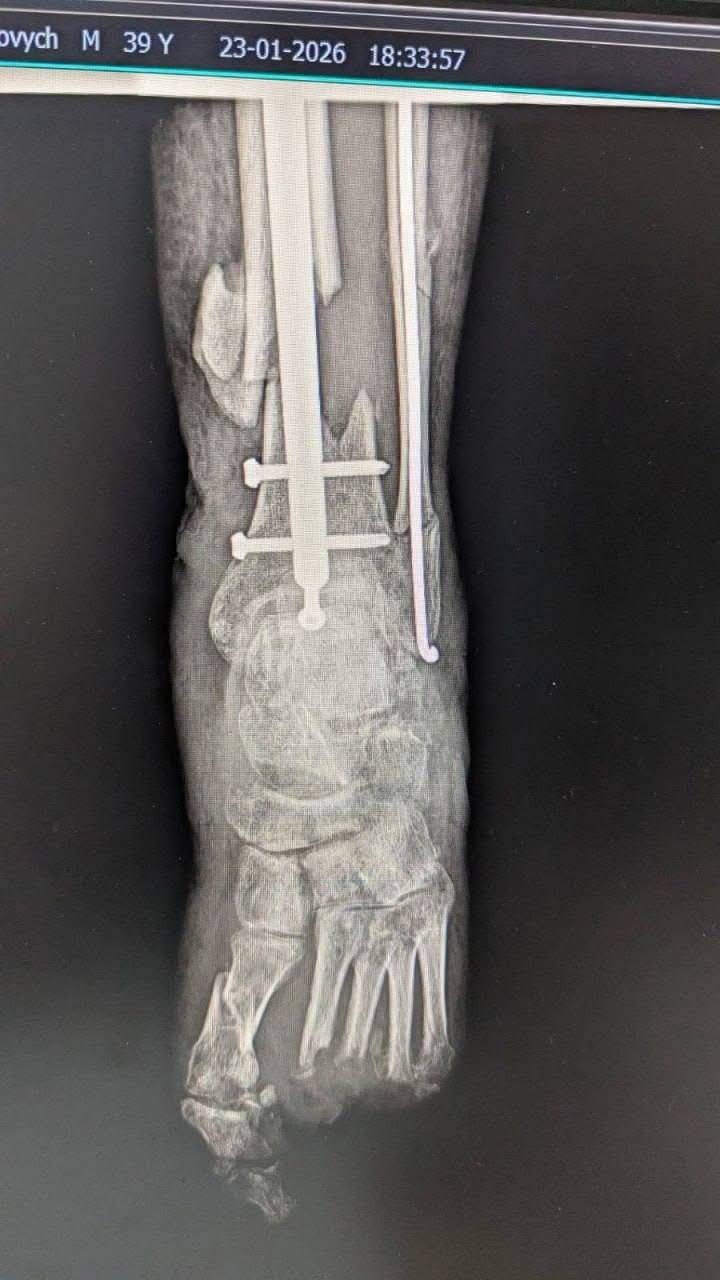

Команда травматологів-ортопедів Богородчанської центральної лікарні провела складну реконструктивну операцію для військовослужбовця з післятравматичним дефектом кістки.

Для лікування пацієнта хірурги застосували сучасну методику: поєднання аутокісткової пластики (використання власної кісткової тканини пацієнта) із біоактивним склом.